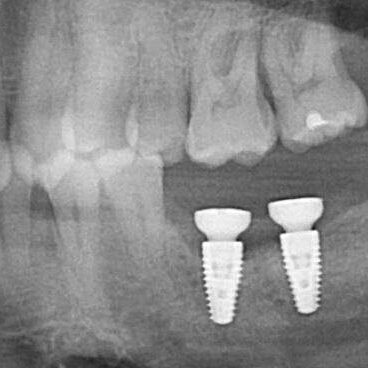

ULTRASONICS: Complications of Abutment Screw Retrieval Secondary to Prior Ultrasonic Attempts

There has been much written on the use of ultrasonics in retrieving fractured screw fragments, which I didn’t think a lot about until May of 2023, as it has not been a part of my fractured screw retrieval algorithm.